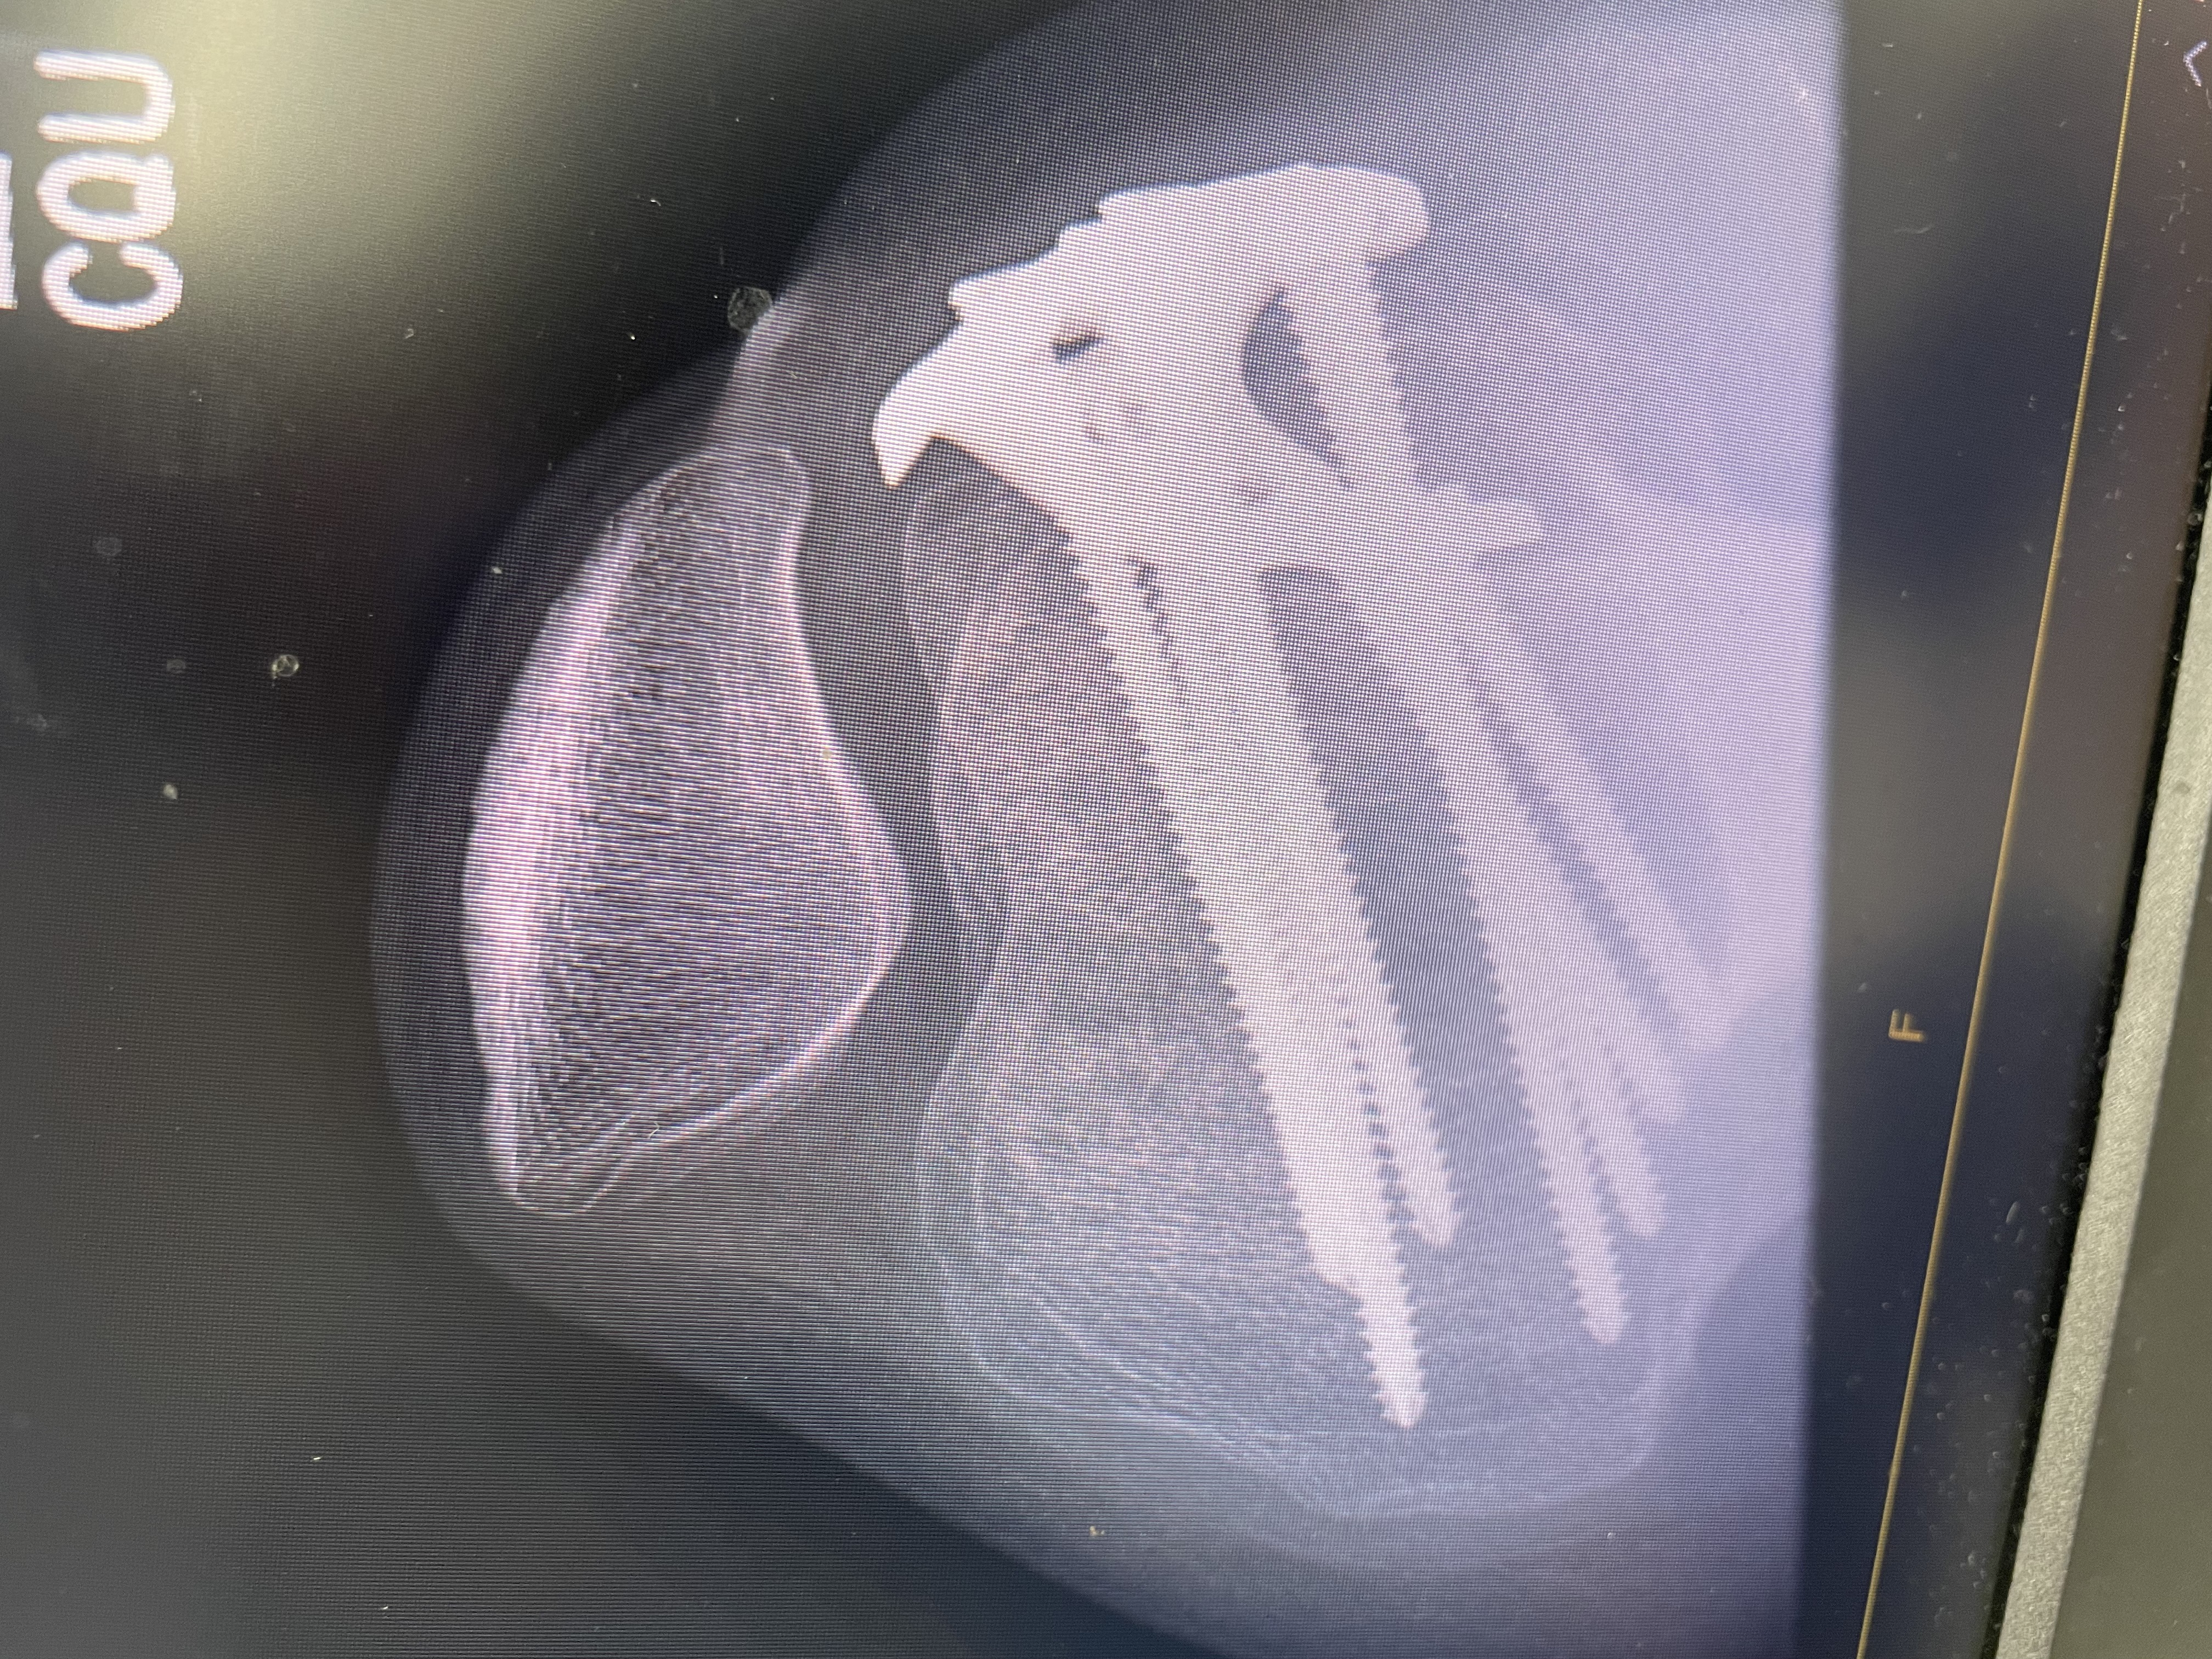

Last May, while I was out dog walking (my job and absolute passion!), one of my clients’ dogs accidentally crashed full speed into my leg. The impact was so strong it fractured my left tibia. I needed orthopaedic surgery to repair the break, and I now have a large metal plate and 8 screws holding my leg together.

Recovery hasn’t been easy. I’ve done everything I can to heal and get back to normal, but the metal hardware has been causing ongoing pain, discomfort, and limited mobility. My doctor has said I’m now eligible to have the plate and screws removed (YAY) — something I’ve been looking forward to for months.